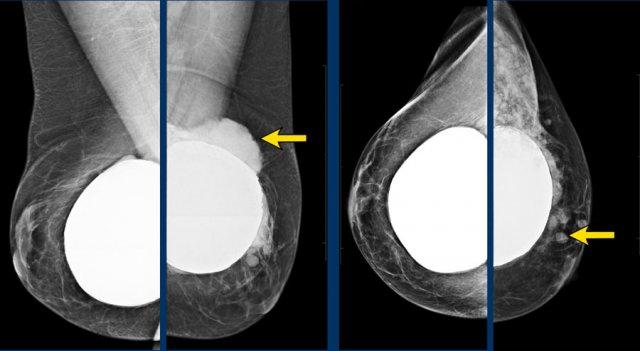

Tư thế chụp chếch của vú phải cho thấy túi ngực chứa nước muối sinh lý bị vỡ và xẹp.

Bên trái là hình ảnh túi ngực chứa nước muối sinh lý bình thường với van bơm.

Trong hình A, có các vôi hóa bao xơ trước cơ ngực của túi ngực cũ và một túi ngực đặt dưới cơ ngực.

Trong hình B là tình trạng sau phẫu thuật cắt bao xơ và thay thế túi ngực đặt dưới cơ ngực.

Hình ảnh điển hình của silicon ngoài bao xơ biểu hiện dưới dạng các khối đậm đặc, bờ rõ nằm ngoài bờ viền của túi ngực.